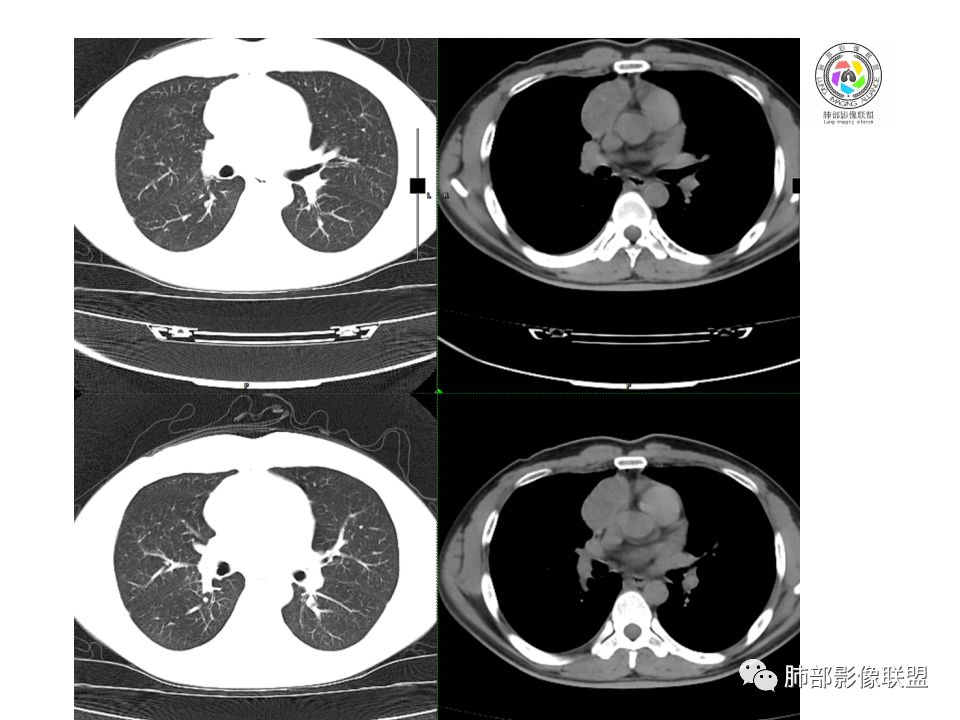

晨读:前纵隔占位,密度不均,沿着右侧纵膈延伸到肺门水平,周围支气管推移,大血管向内推移。临床有重症肌无力,考虑胸腺瘤可能,鉴别淋巴瘤。

患者青年人,前纵隔占位,无增强,猜一个淋巴瘤,不知道右下肺膨胀不全原因是什么

右前纵膈肿块,偏一侧生长,形态欠规则,密度不均匀,其内可见小点状钙化,双肺多发小叶中心结节及钙化灶,右侧胸膜增厚(有陈旧性结核可能),青年男性(27岁),没有增强,考虑,1,前纵隔生殖细胞瘤2,精源细胞瘤

右前上纵隔占位,瘤肺交界面清楚,提示纵隔来源,其内有点状钙化,右侧胸腔积液,有临床症状,年龄轻,考虑生殖来源可能,胸腺瘤待排,请结合临床相关检查或CT增强进一步检查。

左肺上叶病灶,陈旧性钙化灶,右侧胸水是否与之相符,结核?

前纵隔占位,伴点状钙化;上腔静脉后移位。伴右胸膜局限性增厚,临床有重症肌无力,病人年轻,考虑胸腺瘤可能,鉴别生殖源性肿瘤。

临床症状眼睑下垂,右纵膈占位,偏向一侧,有分叶,跟上腔静脉边界不清,淋巴结肿大,考虑胸腺瘤或胸腺癌

右前纵隔占位,有分隔`低密度、点状钙化,边缘光滑,侵袭心包不明确,伴右胸少量积水,考虑恶性,生殖源性可能大,有视物不清,是否脑转移待查。建议HCG丶AFP检查。鉴别1:胸腺瘤、癌,30一40岁以下,少见,但有眼脸下垂,肌无力,待排除。2:淋巴瘤:侵袭性不强,有点状钙化,不支持。3:畸胎瘤:有低密度丶钙化,建议增强进一步明确。4:神经源性:一般后纵隔常见,不支持。5:LCD:症状少见,可以有树枝状钙化,浆细胞型可以有低密度,增强进一步明确

前纵隔偏侧肿块,病灶内见点状钙化,症状肌无力,考虑恶性,胸腺瘤或神经内分泌癌

没有增强,好像两个病灶,上方三角形的像是胸腺增生。下方肿块,没有增强显得更难了,微钙化,轻度分叶,像有坏死低密度影,右侧少量胸水,胸膜受侵.,有视物模糊眼睑下垂。考虑胸腺瘤B1型及以上、B2型可能或生殖细胞瘤

患者年轻,有肌无力症状,除肿块外,前纵隔密度增高,与心包界限不清,考虑恶性。

前纵隔右区占位性病变,上区与胸腺延续,下区呈分叶状,尽管年龄<30还是首先考虑胸腺瘤,侵袭性可能性大(眼睑下垂不知是否有关)。鉴别主要是生殖细胞类肿瘤,主要是精原细胞瘤。另左肺上叶结核球,右侧胸腔积液,需除外结核性胸膜炎和转移

前纵隔占位性病变,偏向一侧生长,密度不均,可见点状钙化,考虑胸腺瘤,鉴别精原细胞瘤

右前纵隔肿块,边界清楚,密度欠均匀,内似有分隔和低密度区,似有多结节融合,几乎从上到下,年龄较轻,不是胸腺瘤好发年龄,但却有视物模糊,眼睑下垂症状,考虑淋巴瘤?鉴别胸腺瘤?结核?

右前上纵膈肿块,内有点状钙化和少许小片状坏死,局部边界似欠清,右侧胸膜腔少量积液,年轻男性,小于30岁,有重症肌无力,虽然年龄偏轻,仍先考虑胸腺瘤,代排生殖源性肿瘤

晨读前纵隔肿块,偏右侧,密度不均,见点状钙化灶及分隔状低密度影。胸腺瘤>生殖细胞瘤>淋巴瘤

前纵膈占位,上腔静脉受推移,有分叶密度较均匀,结合临床考虑胸腺瘤,待排生殖细泡瘤.淋巴瘤

前中纵隔(胸腺癌区)不规则肿块,密度不均,有坏死区、点状钙化,边缘不会整肿块偏向右侧,向心包流注感,右胸腔少量积水。患者27岁,重症肌无力表现。